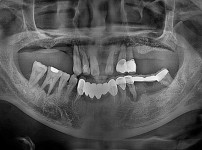

임플란트-전후사진4